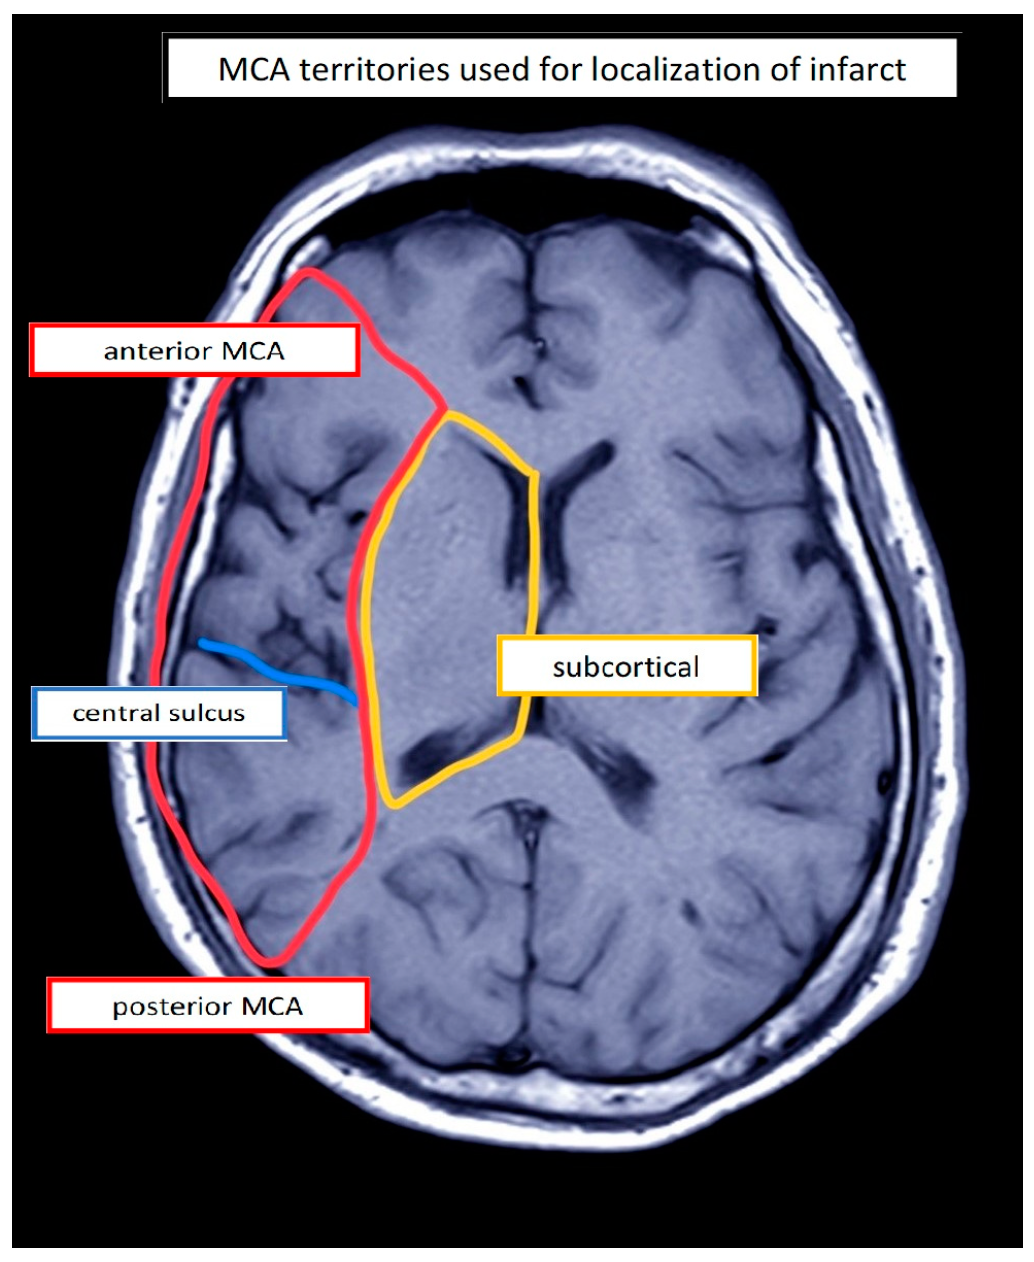

2.2. Participants

4.5. Stimulation Site

| PwA | Etiology | Lesion Location 1 | Stimulation Site (Left) | Sex | Age (Years) | Education (Years) | Duration (Days) | Assessment | Aphasia 2 | Aphasia Severity 3,4 | Initial Severity (ERBI) 5 (FIM) 6 (−325 to +105) (18–126) | |